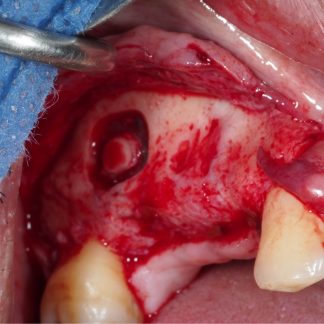

Impacted Tooth Extraction

Price changes 60 minutesImpacted tooth extraction helps in orthodontic cases to accomodate the rest of the teeth. reteined teeth are hidden teeth that could not erupt due to lack of space.Book Quick view -